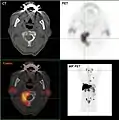

- Projection d'intensité maximale avec divers traceurs

- Projection d'intensité maximale d'un TEP/scanner avec de la choline. On reconnaît clairement l'enrichissement physiologique dans le foie, le pancréas, les reins, la vessie, larate, la moelle osseuse et les glandes salivaires. La métastase osseuse se trouve dans le pubis à gauche.

- TEP/scanner d'intensité maximale avec du fluorodésoxyglucose (18F) (FDG) avec un cancer du sein en métastases. Tumeur primaire dans le sein droit. Métastases dans les ganglions lymphatiques du médiastin et dans les poumons. Les métastases osseuses sont mieux délimitées dans la vue avec 18F-NaF (vidéo suivante).

- TEP/scanner au maximum d'intensité avec du 18F-NaF (fluorure de sodium) sur un cancer du sein en métastases dans le crâne, la colonne vertébrale, le bassin, les côtes, la clavicule gauche et le fémur droit. Même patiente que dans la vidéo précédente (FDG).

Les métastases osseuses de divers cancers peuvent être très bien visualisées par TEP/scanner. Le procédé est plus sensible que la TEMP et notablement plus que la scintigraphie, cependant, plus sophistiquée, et donc plus onéreuse. Selon de type de tumeur primitive, on utilise divers traceurs, mais le plus souvent le Fluorodésoxyglucose (18F) et le fluorure de sodium NaF (18F), et aussi pour le cancer de la prostate la choline (18F). L'activité métabolique de la tumeur est le plus souvent bien visible avec le FDG, et la réaction de l'os à la métastase avec le NaF[124].

- TEP/scanner à la choline 18F

Métastases ostéolytiques dans la deuxième vertèbre du cou (Axis) d'un cancer de la prostate.

Métastase ostéocondensante d'un cancer de la prostate dans la hanche

Scanner d'une métastase d'un cancer de la prostate à gauche dans le pubis (à dr. sur l'image)

TEP de la même métastase au pubis

Image composite scanner/TEP de la même métastase